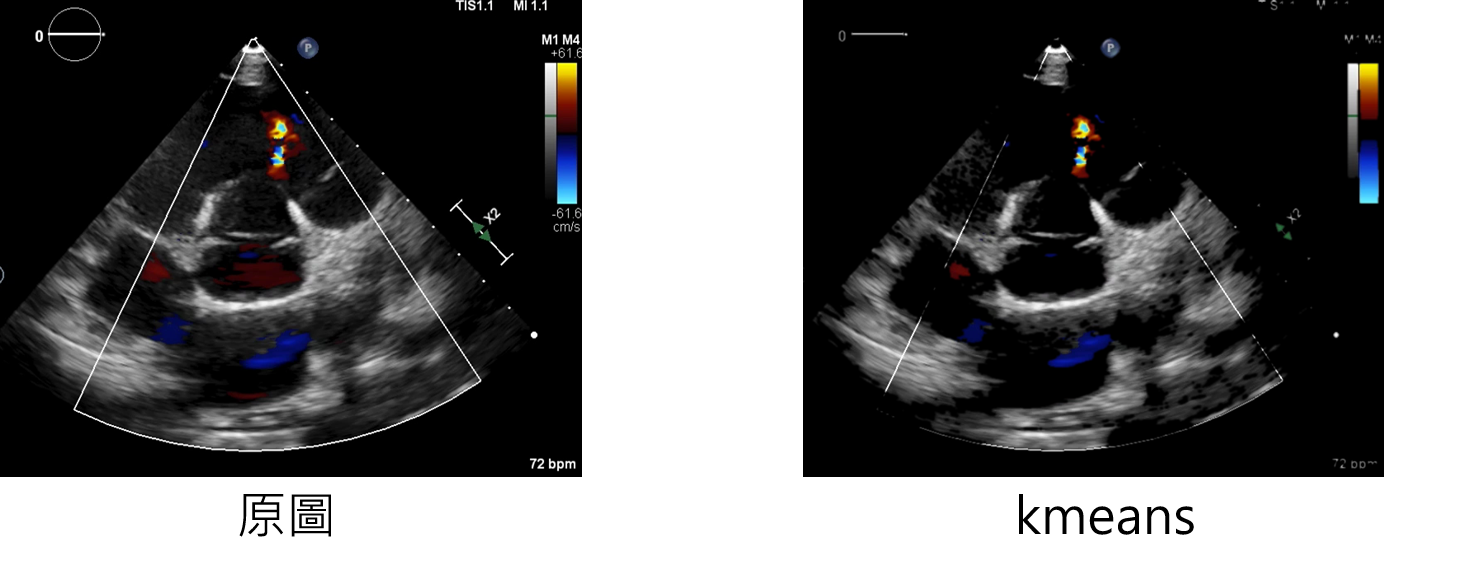

下方介紹圖像去背方法分別為,小波轉換、k-means

參數說明

kmeans:增強方法

num_clusters:獲得每個像素所屬的類別

輸入範例:

datagen=CustomDataGenerator(fun="kmeans",num_clusters=4,dtype=int)

-

注意!!!!

該方法因為輸出為單通道,因此無法在本專案做使用。